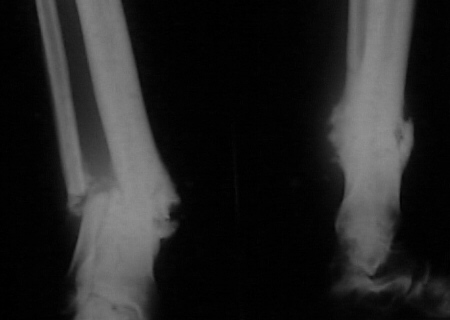

It seem a stiff pseudarthrosis. I will do a axial correction and lengthening if necessary with Ilizarov frame without any corticotomy. Probability of success will be 100% and relapse of infection 0%. You can see one case attached.